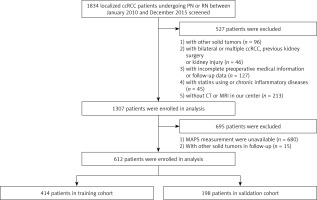

In close compliance with the inclusion criteria, 612 patients with localized ccRCC who underwent surgery from January 2010 to December 2015 were incorporated and randomly divided into a training cohort (n = 414) and a validation cohort (n = 198) (Figure 1).

Figure 1

Patient selection flowchart

ccRCC – clear cell renal cell carcinoma, CT – computed tomography, PN – partial nephrectomy, RN – radical nephrectomy, MRI – magnetic resonance imaging, MAPS – Mayo adhesive probability score.